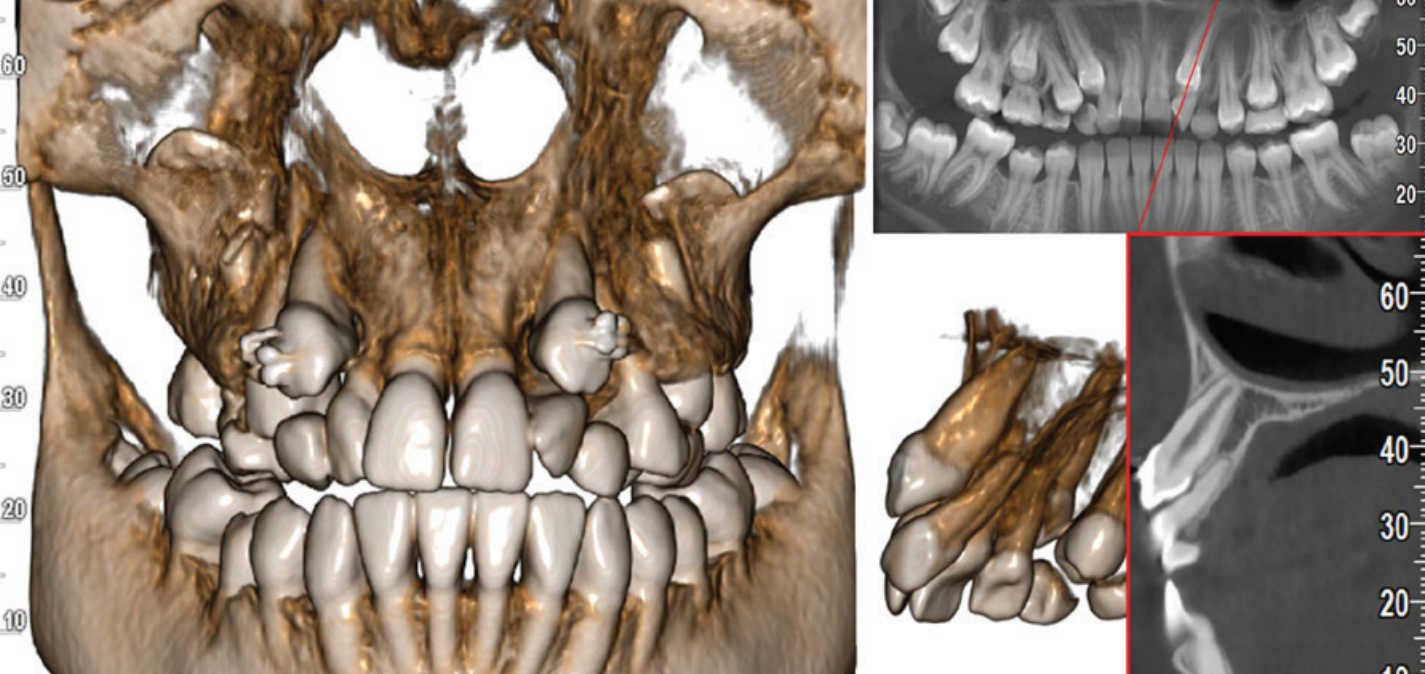

Yeni nesil hassas Cmos Flat Panel Teknolojisi. Görüntü kesitleri eskiye göre 2 kat daha keskin ve net görüntü almayı sağlamaktadır. Panoramik görüntülemede devrim yaratan Panoral 5 MultiPan çekim tekniği ile tek panoramik doz ile 5 ayrı katmanda görüntü alınır. Reel 16 bit yüksek gri skalası ile yüksek çözünürlük ve kesin tanı imkânı sunmaktadır. PANORAL 5 MULTIPAN Panoramik Röntgen Çekim Tekniği: CMOS Flat Panel Hassas Sensör teknolojisi tek bir panoramik doz ile horizontal düzlemde 3 mm. aralıkla, hastanın 5 ayrı vertikal panoramik görüntüsünün elde edilmesini sağlamaktadır. Bu şekilde net alan derinliğine girmeyen bir diş var ise bir önceki veya bir sonraki filmde görülebilir. Panoral 5 MULTIPAN görüntüleme tekniği; maloklüzyon ve hasta pozisyonlandırma hataları nedeniyle oluşabilecek görüntü bozukluklarını elemine edebilmektedir. Böylelikle panoramik röntgen çekimlerinde pozisyonlandırma hatalarına bağlı çekim tekrarlarına da gerek kalmaz.

Endodontik değerlendirmeler için sadece ilgili bölgedeki ayrıntılı teşhisler yapılabilmektedir. 2D görüntülerden çok daha derinlemesine gömülü dişler arasındaki ilişkilerin neredeyse bir periapikal dozunda incelenmesi sağlar.